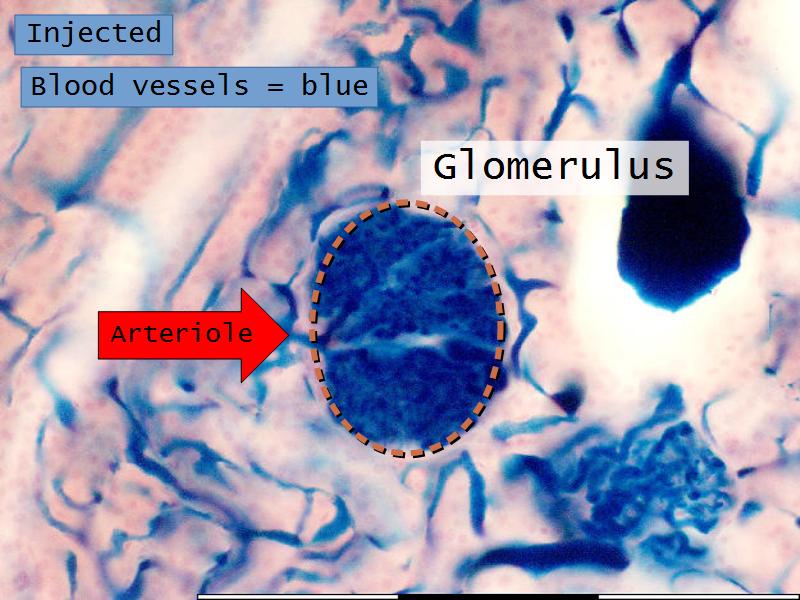

Slides 28 & 76

- Structure of the nephron and collecting tubules

- The renal corpuscle